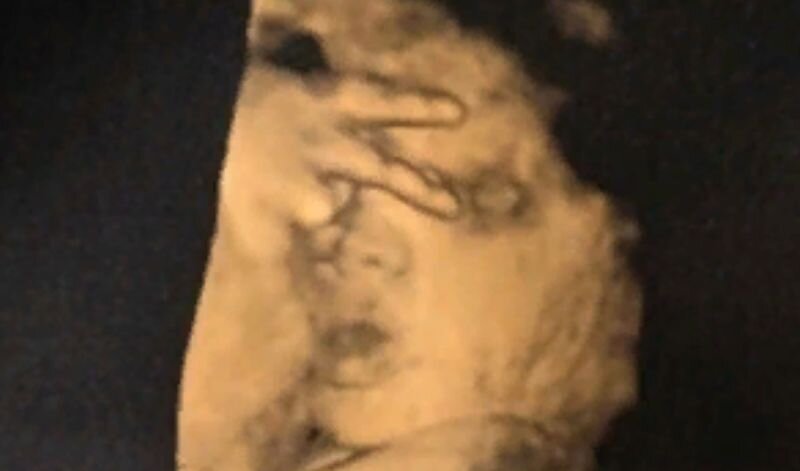

Шокировал врачей: ребенок на УЗИ показал «знак победы»

Во время очередного УЗИ врачи некоторой клиники в Пейсли (Шотландия) были шокированы, увидев жест, который продемонстрировал ребенок 21-летней Джеммы Хьюстон. Так, малышка показала рукой «V», то есть знак победы, сообщает портал PLANETANOVOSTI.COM со ссылкой на Mirror Online. Это было четвертое УЗИ женщины. Оно запомнилось не только будущей маме, но и врачам. Джемма начала смеяться в кабинете врача, тогда как сами специалисты были в замешательстве. Интересно, что во время таких процедур девочка никогда не принимала правильного положения, чтобы доктор мог осмотреть её. На данный момент Джемма не имеет ни одной нормальной фотографии не родившегося еще ребенка. Женщина уверена, что её дочка станет настоящей дивой, она характером будет похожа на маму. Джемма отметила, что обязательно покажет сделанный снимок УЗИ своей дочке в будущем. Интересно, что в Сети нередко появляются различные смешные и не очень казусы, связанные с УЗИ.